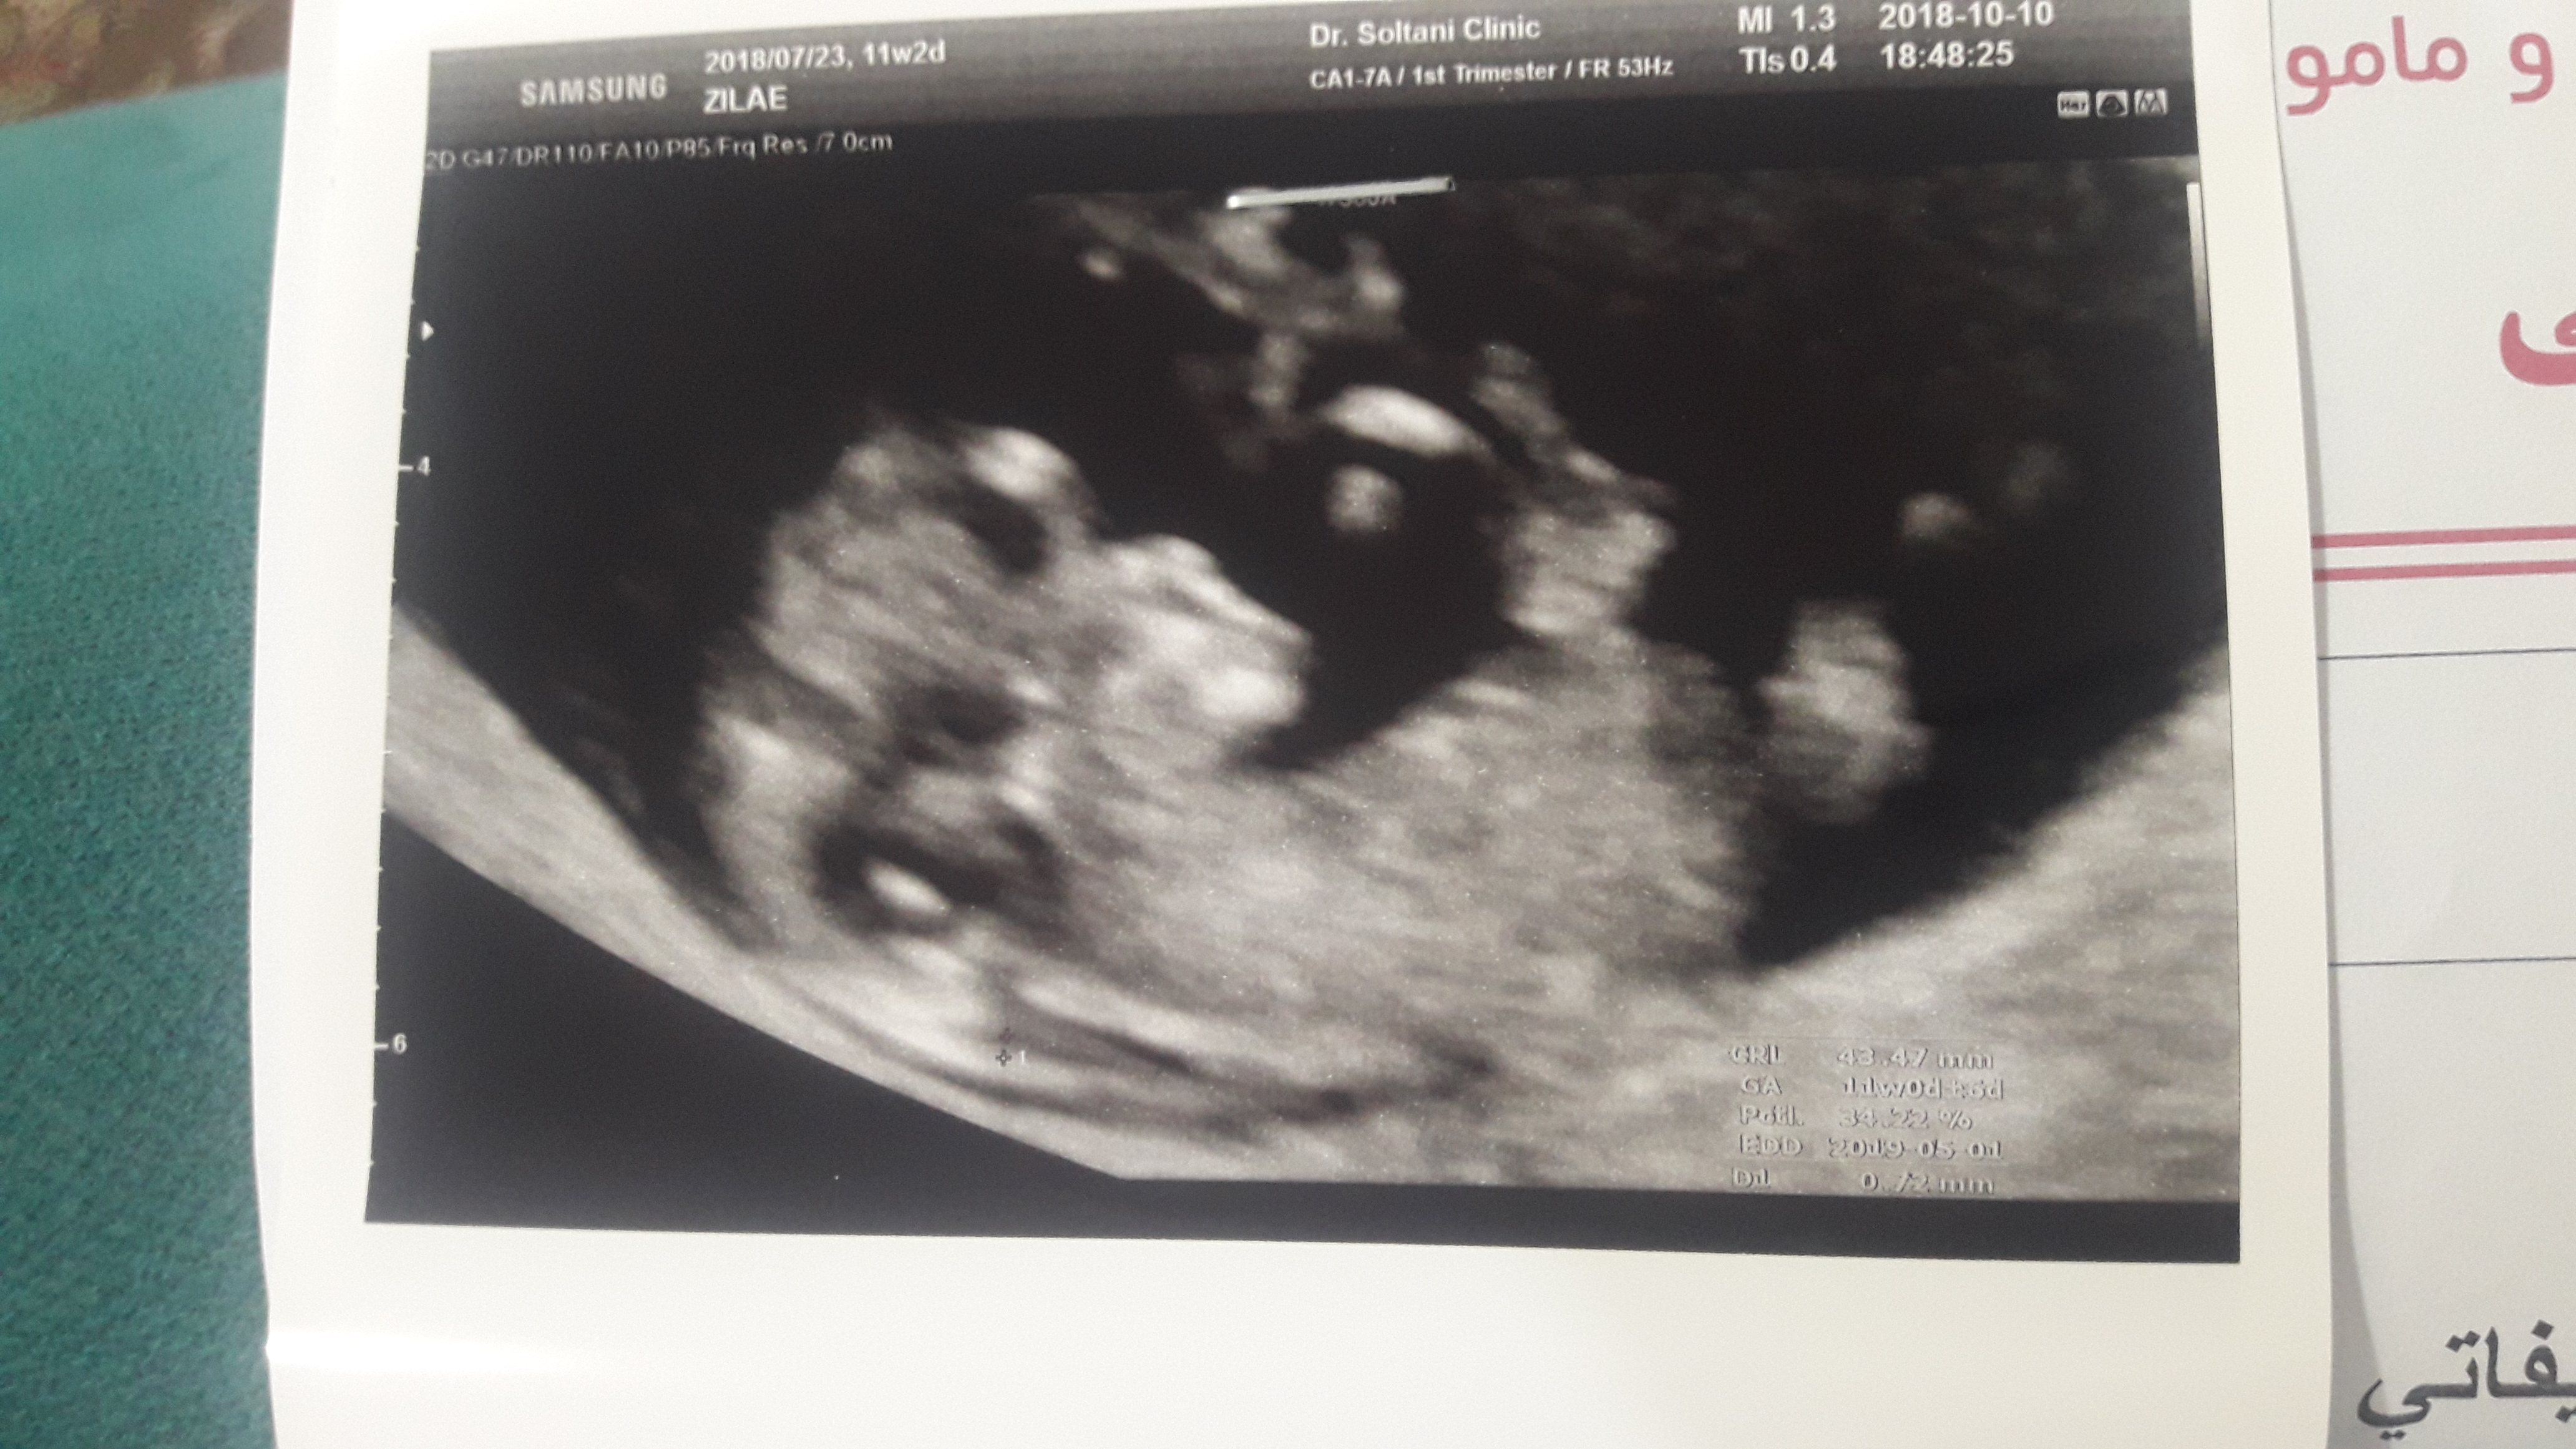

سونوگرافی که از رو یه عکس نیست،از روی فیلمه و بلید زاویه های مهتلفی بررسی بشه،اون عکسو که میزارن فقط واسه اینه که اثبات کنن سونوگرافی انجام دادن وگرنه لینو دست بهترین سونوگرافیست جهانم بدی نمیتونه برات هیچی‌ازش دربیاره

سونوگرافی که از رو یه عکس نیست،از روی فیلمه و بلید زاویه های مهتلفی بررسی بشه،اون عکسو که میزارن فقط ...